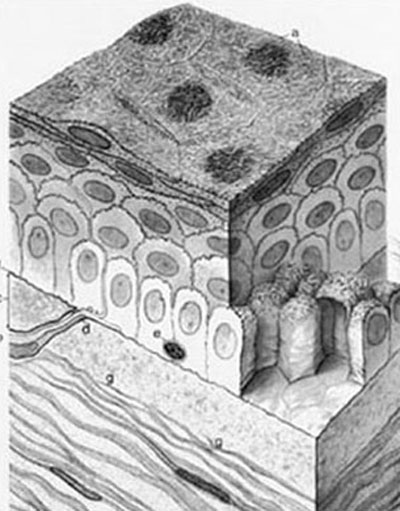

Epitelio. (a)

Es la capa más externa y está en contacto con la película lagrimal. Formada por 5-7 capas de células, que siendo de forma cúbica en las capas profundas se van aplanando a medida que se hacen superficiales. Tiene un espesor de ± 50 a 52 µm Su función al igual que otros epitelios es de protección contra el entorno, impide la pérdida de liquido y la entrada de elementos nocivos. Es una capa de recambio rápido ± 5 a 7 dias que se va eliminando por descamación. Tiene una capacidad de respuesta a la agresión rápida y muy especializada. La sensibilidad está relacionada con una extraordinaria densidad en terminaciones nerviosas que se calcula, puede ser 300 ó 400 veces mayor que la de la epidermis de la piel. Se cree que las células madre del epitelio corneal están situadas en las células basales del limbo epitelio-conjuntival.

Ilustración de las Estructuras del Epitelio

Capa de Bowman. (c)

Es una matriz acelular de colágeno extracelular, producto de síntesis coordinada entre el epitelio y las células del estroma y separa el colágeno estromal del epitelio.

Estroma. (g)

Representa el 90% del espesor de la córnea. Esta conformada por láminas entrecruzadas de colágeno enbebidas en mucosubstancias.